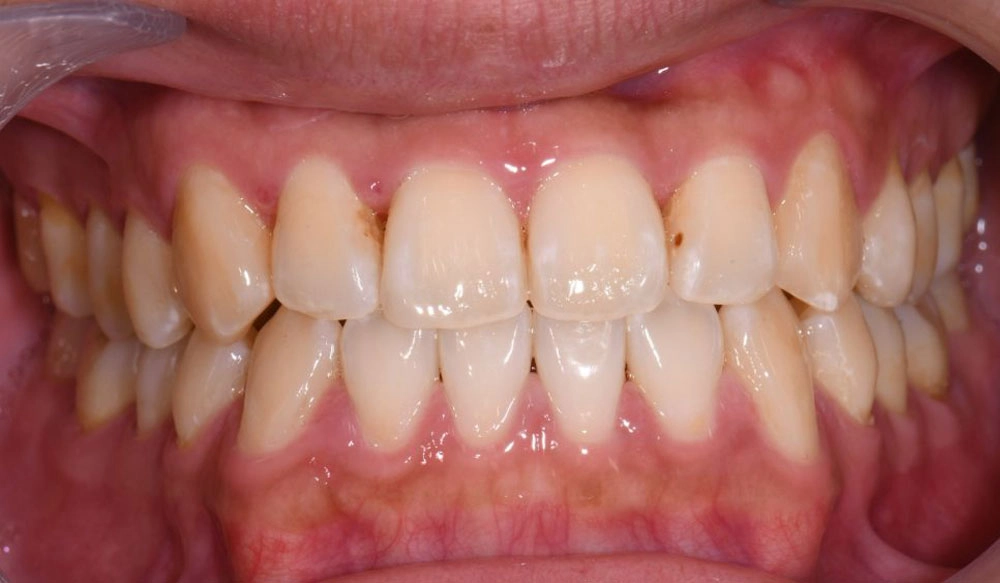

Midline Discrepancy

Midline discrepancy is the condition in which there is a misalignment of the midsagittal line of maxillary and mandibular arches respectively and/or relative to the facial midline.

Patient Information:

Age: 28

Gender: Female

Invisalign Treatment Option: Invisalign Comprehensive

Total Treatment Time:

16 months